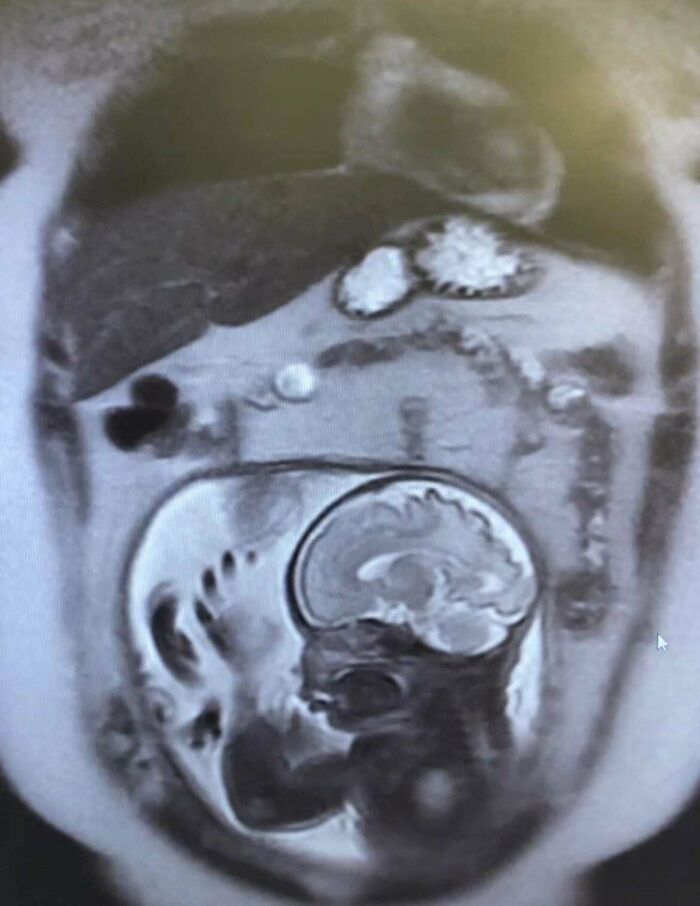

An MRI View You Won’t See Everyday